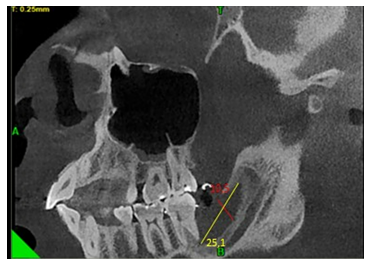

En el corte oblicuo, también se observó una imagen hiperdensa compatible con crecimiento óseo en unidades métricas desde el borde anterior de la mandíbula hacia la basal mandibular de 10.5 mm y en sentido postero-anterior de 25.1 mm, con lo cual se obtuvieron medidas más exactas el crecimiento óseo ganado y en una imagen hiperdensa se aprecia el techo del conducto dentario inferior.

Figura 9 Corte de tomografía computarizada de haz cónico, en donde se evidencia en vista oblicua una imagen hiperdensa compatible con crecimiento óseo. Medidas referenciales 10.5 mm x 25.1 mm. Fuente: Historia Clínica. Especialización Cirugía Bucal ULAC-IDOLA. 2022